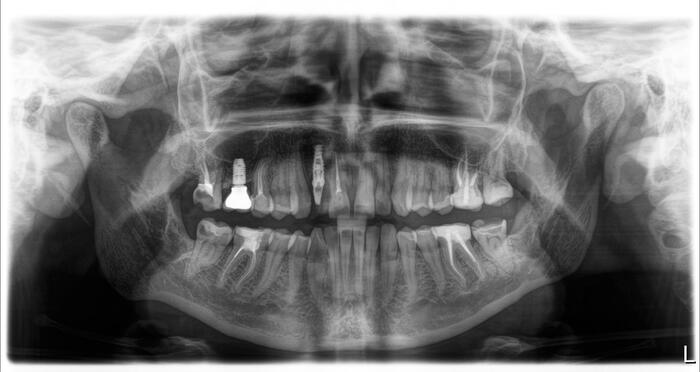

Согласитесь, не особо эстетично. Ортопантомограмма:

Контрольная ортопантомограмма:

Прицельный снимок:

Я согласен, что эстетика хромает. Давно пора менять временную коронку на постоянную, что улучшит результат. Но, как я говорил, все упирается в финансы.